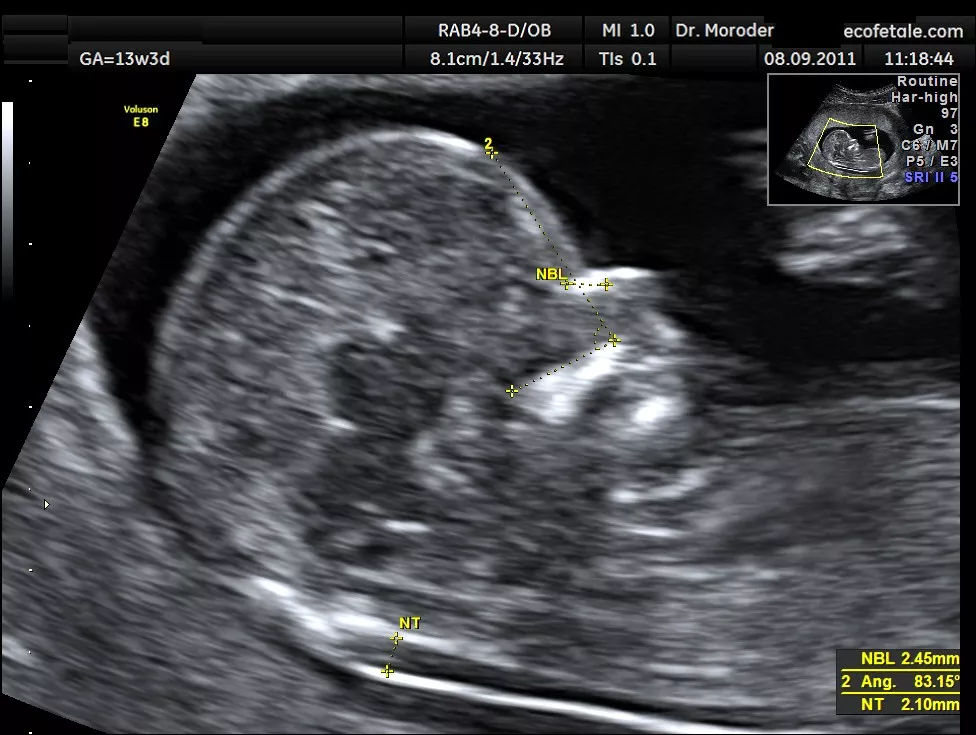

患者,女性,25岁,0-0-0-0,末次月经2020年4月20日,预产期2021年1月27日,孕7周B超提示CRL:0.5cm,及心搏。孕期服叶酸片,孕早期稍有恶心呕吐,无保胎史,孕12周做NT提示NT值2.6mm,见鼻骨,CRL:6.0cm。

先来给出一个明确的答案:绝大部分NT值为2.6mm的胎儿是正常的,但是也存在个别异常,NT值增高的风险指的是比正常的胎儿患非整倍体染色体异常和胎儿心脏结构异常的概率要大,正因为这个原因,建议可以选择做一个无创DNA检查及胎儿心超(20-24周)。至于羊水穿刺,如果没有早唐筛查高风险或临界风险,或者后续的超声软指标异常,不建议做,为什么,原因就是没有到那个地步,收益比不够,而且羊水穿刺属于有创,会大致妊娠丢失(流产)。但是当NT大于等于3.5mm或者伴有其他风险时,我就会毫不犹豫的推荐你做羊水穿刺,应该收益比增加了。但是为什么有些医生动不动就叫做羊水穿刺,毫无对她来讲做羊水穿刺更合适(撇清风险),因为可以百分百的排除胎儿染色体异常,对她自己没有任何风险,但是对你却不适用,因为羊水穿刺属于有创操作有风险。专业的终归是专业的,孕12周,CRL6cm,得出的NT第95位数应该是2.2mm,故NT2.6mm属于异常。

NT是一种筛查胎儿非整倍体染色体异常和胎儿心脏结构异常的手段。主要通过B超测量胎儿颈项透明层厚度来判断胎儿是否存在异常。而且B超测量是统一化的,要不然测量的结果就参差不齐了,推荐到正规的医院进行测量。

至于时限性,NT也是有时限性的,假如超过一定时限,那么它将毫无意义,目前我国的时限为孕11-13+6周,且需要满足CRL4.5-8.4cm。宝妈们一定要记得在这个时间段内产检,过期作废。温馨提示别太在意NT值,毕竟只是怀疑胎儿异常的一种手段,而不是确诊手段。其实更适用于联合早唐筛查。NT值更多的是筛查21-三体,18-三体,13-三体。